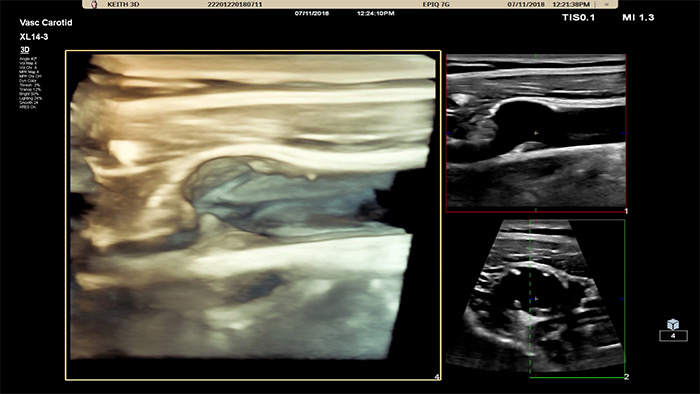

3D/4Dユーザーインタフェースは、フローデータを使用したVessel Cast生成機能も備えています。3D Vessel Cast生成機能により、フローを直接描出して、狭窄や蛇行状態を詳しく観察することができます。主なメリットとして、血管構造を高画質の3D/4Dで描出できるため、医療従事者の間で臨床的判断を促進し、患者本人による病状理解を促すコンサルテーションを強化する理想的なコミュニケーションツールとなる点が挙げられます。